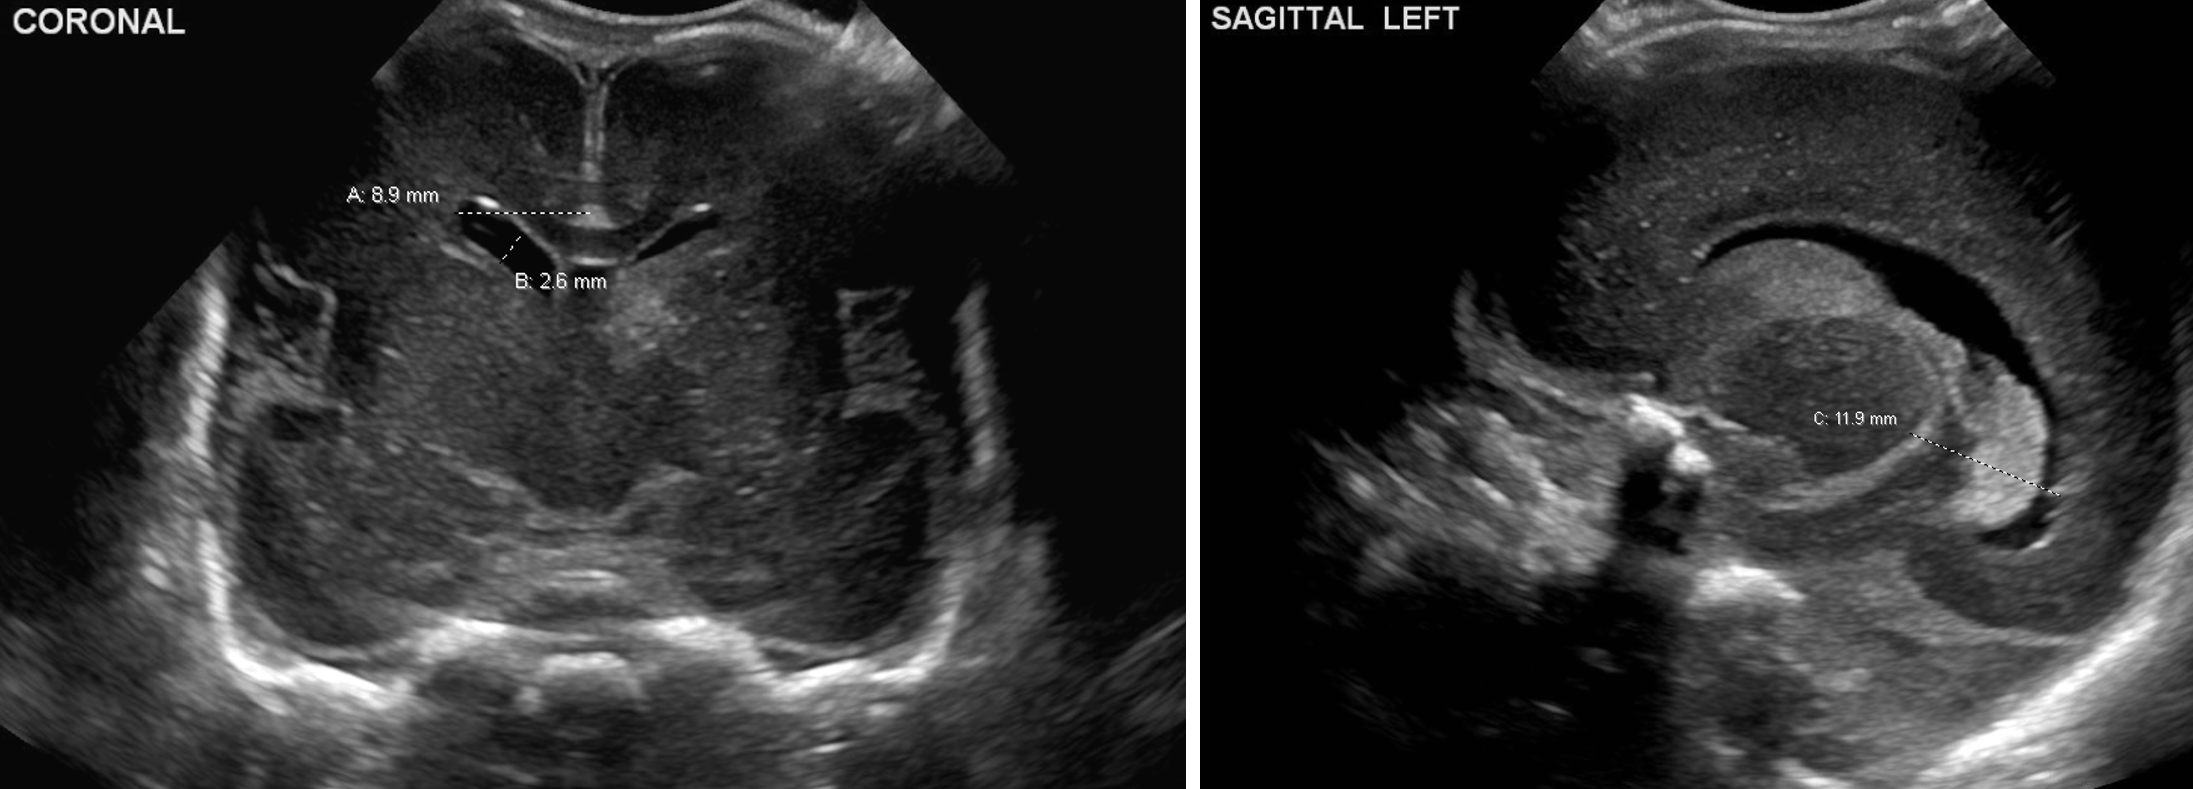

Age: 4 days (born at 24 weeks)

Sex: Male

Indication: Evaluate for germinal matrix hemorrhage

Grade 2 germinal matrix hemorrhage

Sample ReportLeft germinal matrix hemorrhage involving the caudothalamic groove and layering in the occipital horn of the left lateral ventricle without hydrocephalus (grade 2).

No abnormal brain parenchymal echogenicity or extra-axial collections.

Premature sulcation pattern.